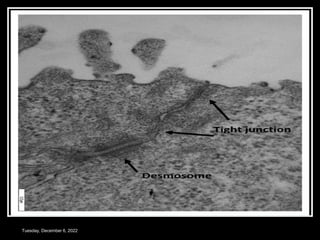

TIGHT JUNCTIONS

 Called Zona occludens

or occluding zone

 Outer layer of PL fused

with each other

 Obliterate the space

between cell

 Does not allow

transport/movement of

ions or other solutes.

ADHERENS JUNCTIONS

 Zona adherens

 Cell adhere to each

other by dense

accumulation of

proteins at cell surface

 Types

 Desmosomes – both

cells

 Hemidesmosomes –half

Tuesday, December 6, 2022